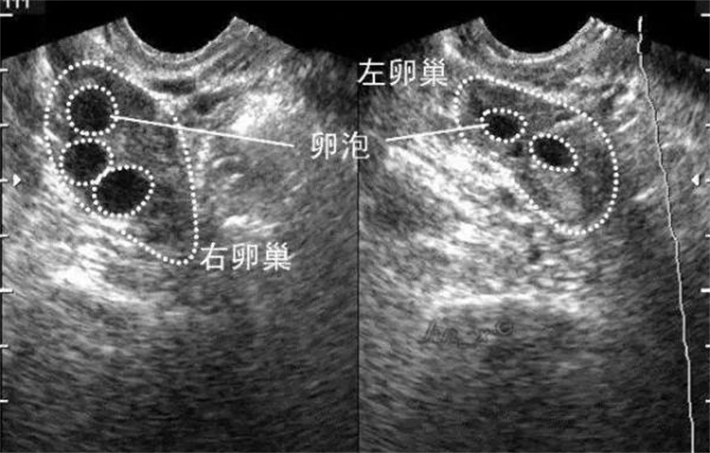

从生理规律来看,女性月经周期分为卵泡期、排卵期、黄体期,月经第2-3天正处于卵泡期早期。此时,卵巢内的卵泡还未开始大量发育,处于“休眠”状态。通过B超监测,HRC专家可以清晰地看到卵巢内基础卵泡的数量。基础卵泡数量越多,说明卵巢储备越好,促排时能取出优质卵子的概率就越高;反之,若基础卵泡数量过少,则提示卵巢储备下降,需要调整促排方案,避免无效促排。

除此之外,这个时间点的卵巢大小、形态也能更真实地反映其功能状态。如果卵巢体积偏小、形态不规则,结合基础卵泡数量,HRC专家可以更精准地判断卵巢储备情况,提前制定针对性的助孕策略。

很多姐妹会问:“月经第2-3天还在流血,做B超会不会有影响?”其实完全不用担心。少量经血不会干扰B超的观察,反而因为子宫内膜薄,能更清晰地看到卵巢内的卵泡,避免因子宫内膜增厚遮挡卵泡,导致计数不准确。